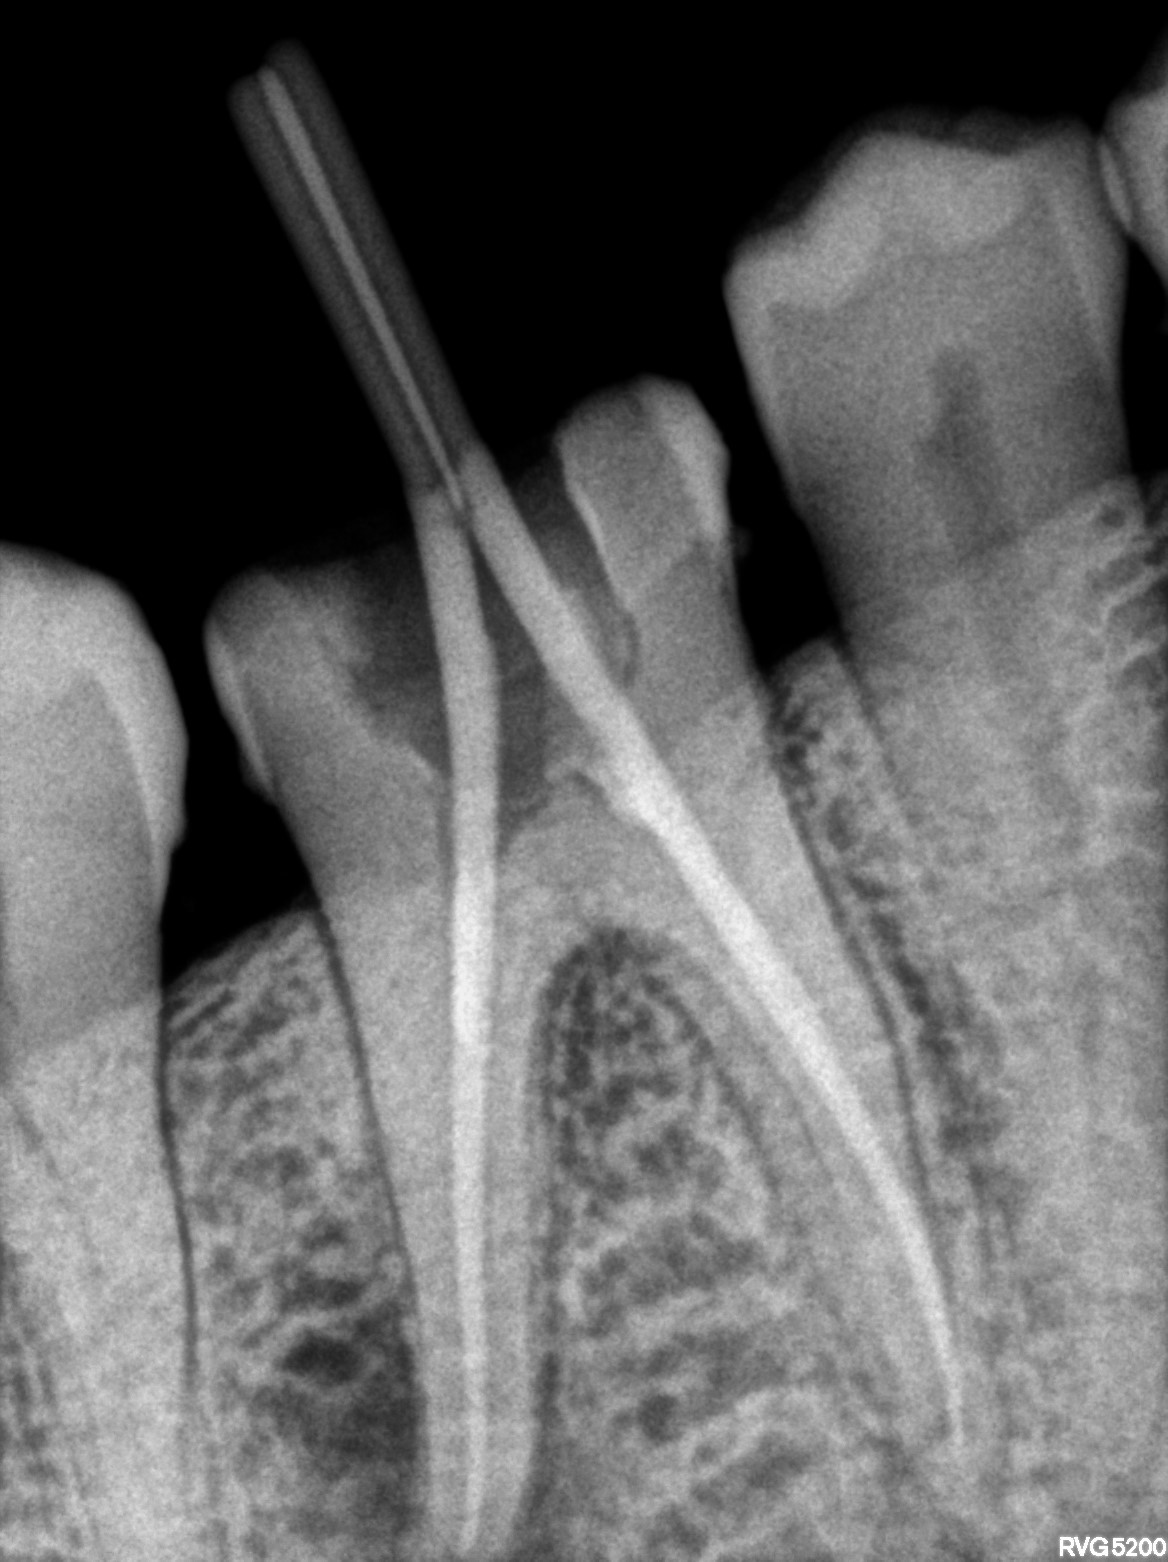

Dental Radiographs FHIR: DocumentReference · LOINC 24641-7

xray_1770481373_1.jpg

24641-7